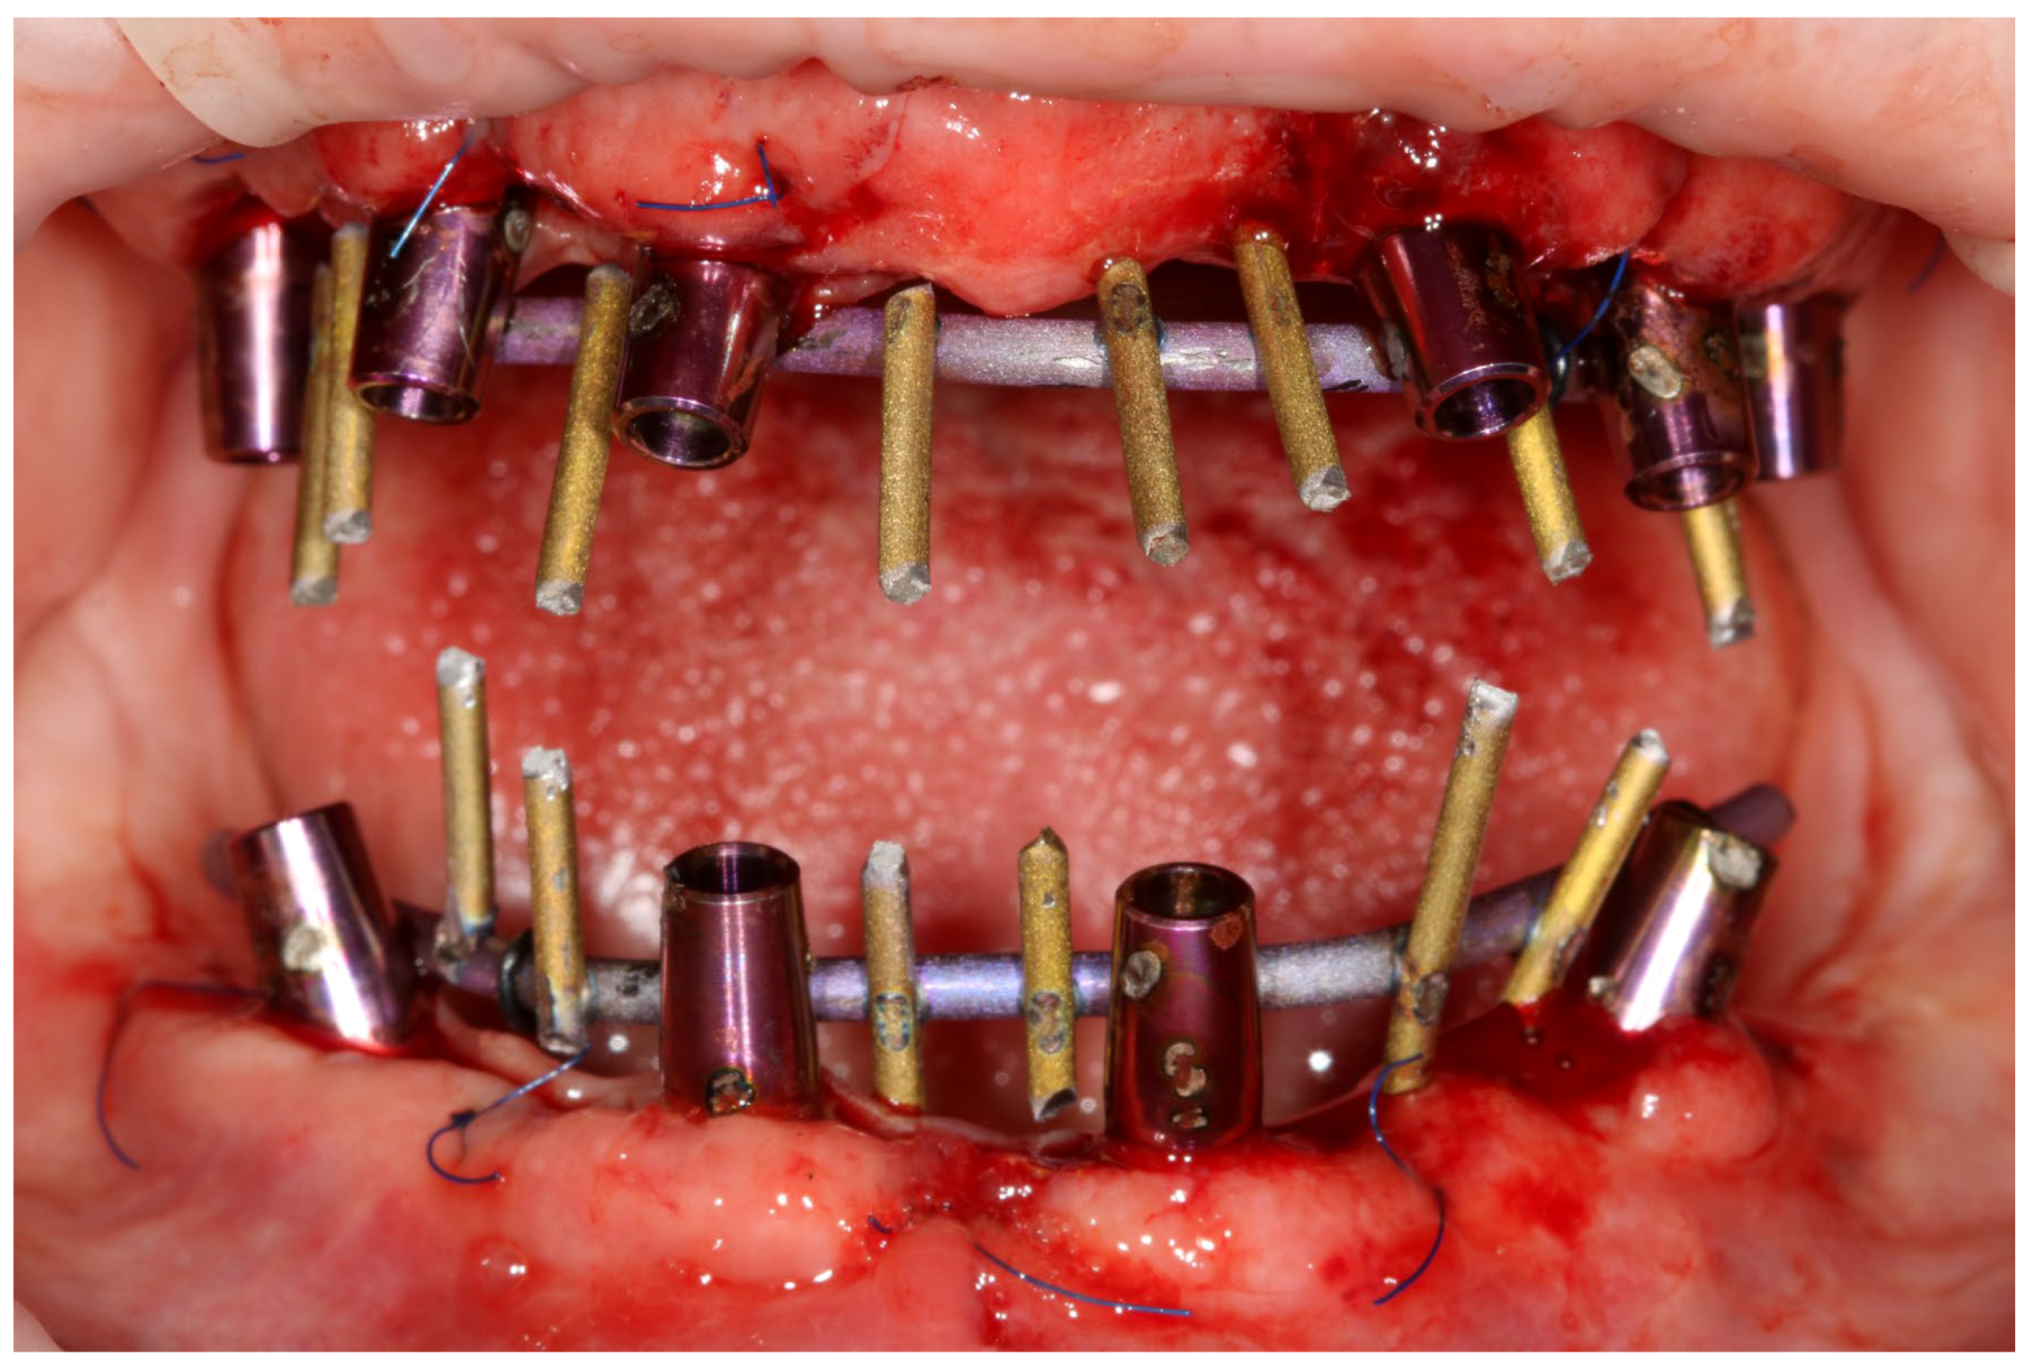

- One-day surgery with implant placement, MUA, and intraoral welding to obtain immediately loaded long-lasting temporaries.